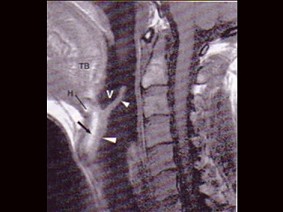

11.MRI检查结果如下图,下一步最重要的检查是  (    )